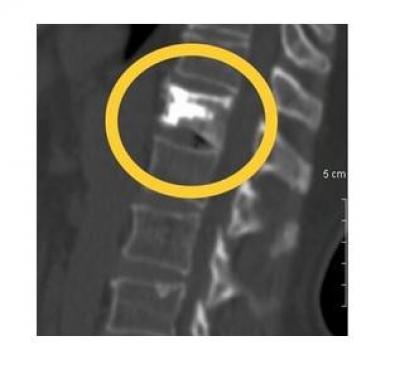

El cemento Spine-fix®, es específico para cirugía de columna de alto medio de contraste radio-opaco líquido. La alta concentración de sulfato de bario permite que sea utilizado durante los procedimientos de los tornillos pediculares y Vertebroplastia o Cifoplastia.